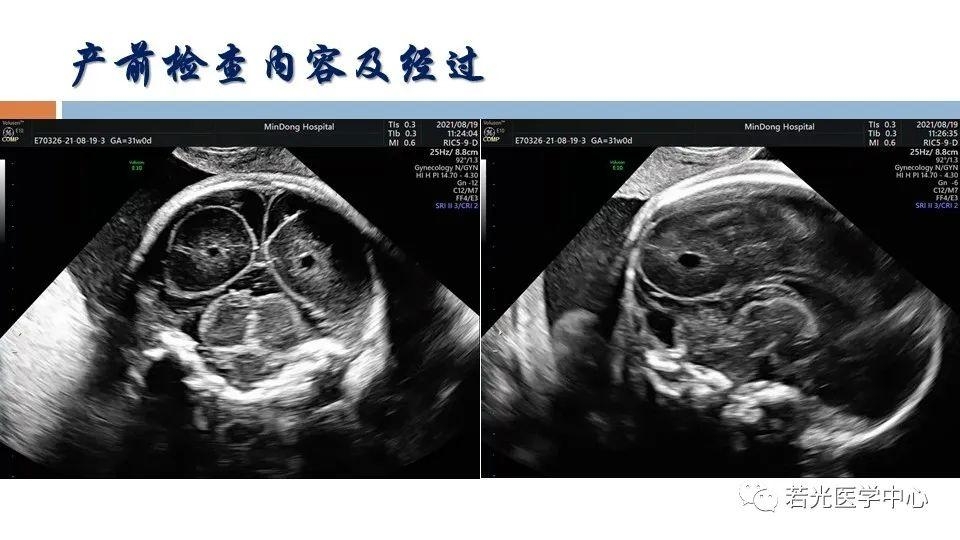

(6)表型-征象-分子遗传联合分析,遗传咨询分析与分子诊断。产前胎儿影像(超声,MRI)等异常,各类胎儿先天畸形与出生缺陷表型-基因-家系遗传分析,产前产后胎儿异常分析咨询,生育健康咨询。